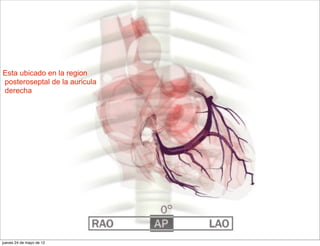

Esta ubicado en la region

posteroseptal de la auricula

derecha

Esta ubicado enla region posteroseptal de la auricula derecha jueves 24 de mayo de 12